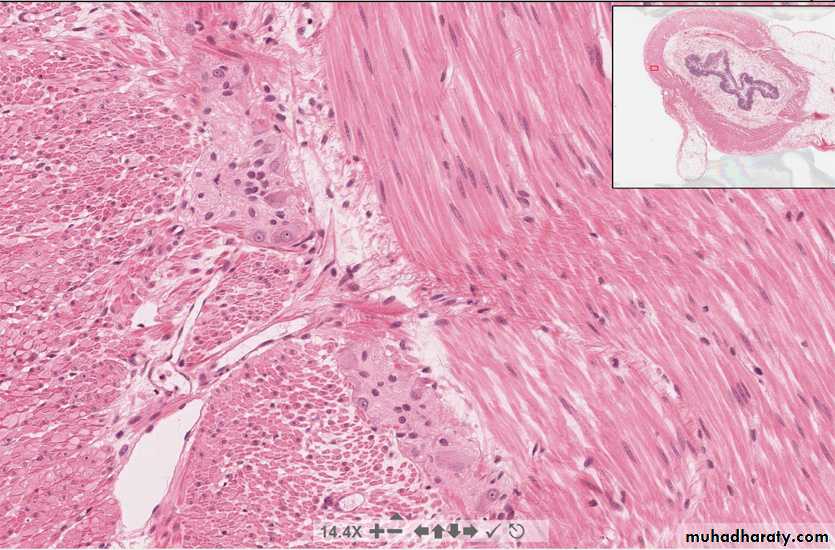

Sympathetic ganglion cells:multipolar neurons that reside entirely within the PNS in sympathetic chain ganglia and “pre-aortic” ganglia

Parasympathetic ganglion cells:multipolar neurons that also reside entirely within the PNSin the wall of the innervated organ (shown here in the seminal vesicle)